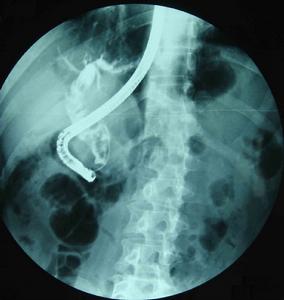

膽總管結石內鏡取出實驗室檢查:在急性梗阻性膽管炎時主要為白細胞增多和中性粒細胞增加等急性炎症的血液像,血膽紅素增高和轉氨酶增高等梗阻性黃疸和肝功受損的表現。若較長時間的膽管梗阻、黃疸或短期內反覆發作膽管炎肝功明顯受損,可出現低蛋白血症和貧血徵象。

5.ERCP和PTC檢查均可清晰顯示膽管系統的全貌,能比較準確提供肝內外膽管和膽囊結石的大小、數量、位置以及肝內外膽管擴張、狹窄等病理改變狀況,是獲得術前準確診斷最重要的檢查方法。ERCP基本無創、併發症較少,PTC為有創、併發症稍多,可根據病人和病變的具體情況選擇。一般情況下多選擇ERCP檢查。